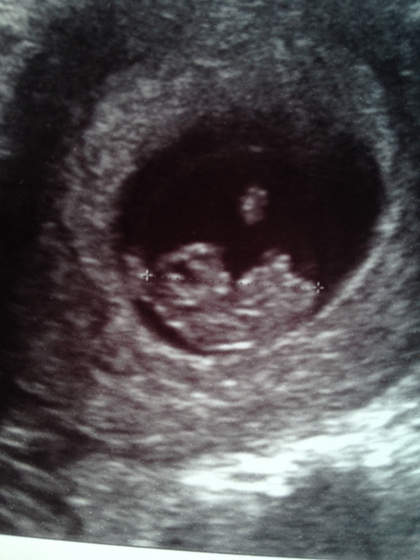

Nie jestem juz fasolka, ale małym człowieczkiem, mam mini nosek, nozki i ramionka. Mierze 22mm. Serducho bije jak dzwon! Byłem bardzo ruchliwy i pokazałem sie ze wszystkich stron, to białe nade mną to pępowina ;D